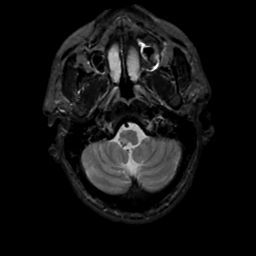

MR Study #1, February 10, 1991 -- Slice #6

[Home][Help][Clinical][Tour 1][Tour 2] Slice 6